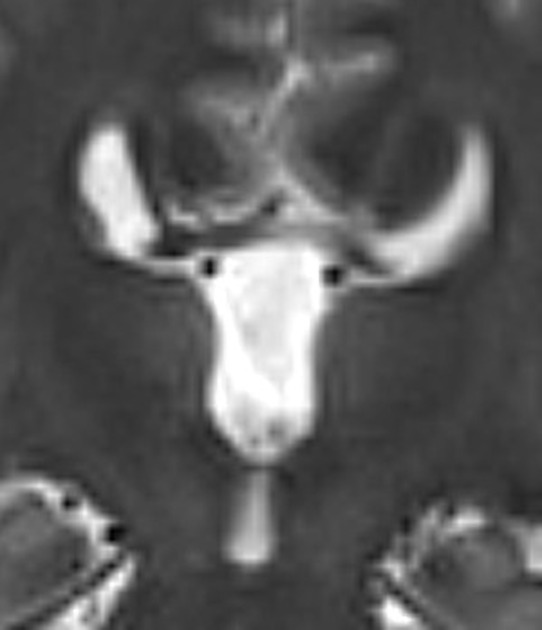

O sinal do alce (moose signal) ou sinal do capacete viking (viking helmet signal) pode ser observado na neuroimagem em indíviduos com digenesia/agenesia do corpo caloso ou desmielinização. Na ressonância magnética em corte frontal, os ventrículos laterais apresentam-se tal qual a cabeça de um alce, e o giro cingulado é evertido em longos e estreitos chifres.